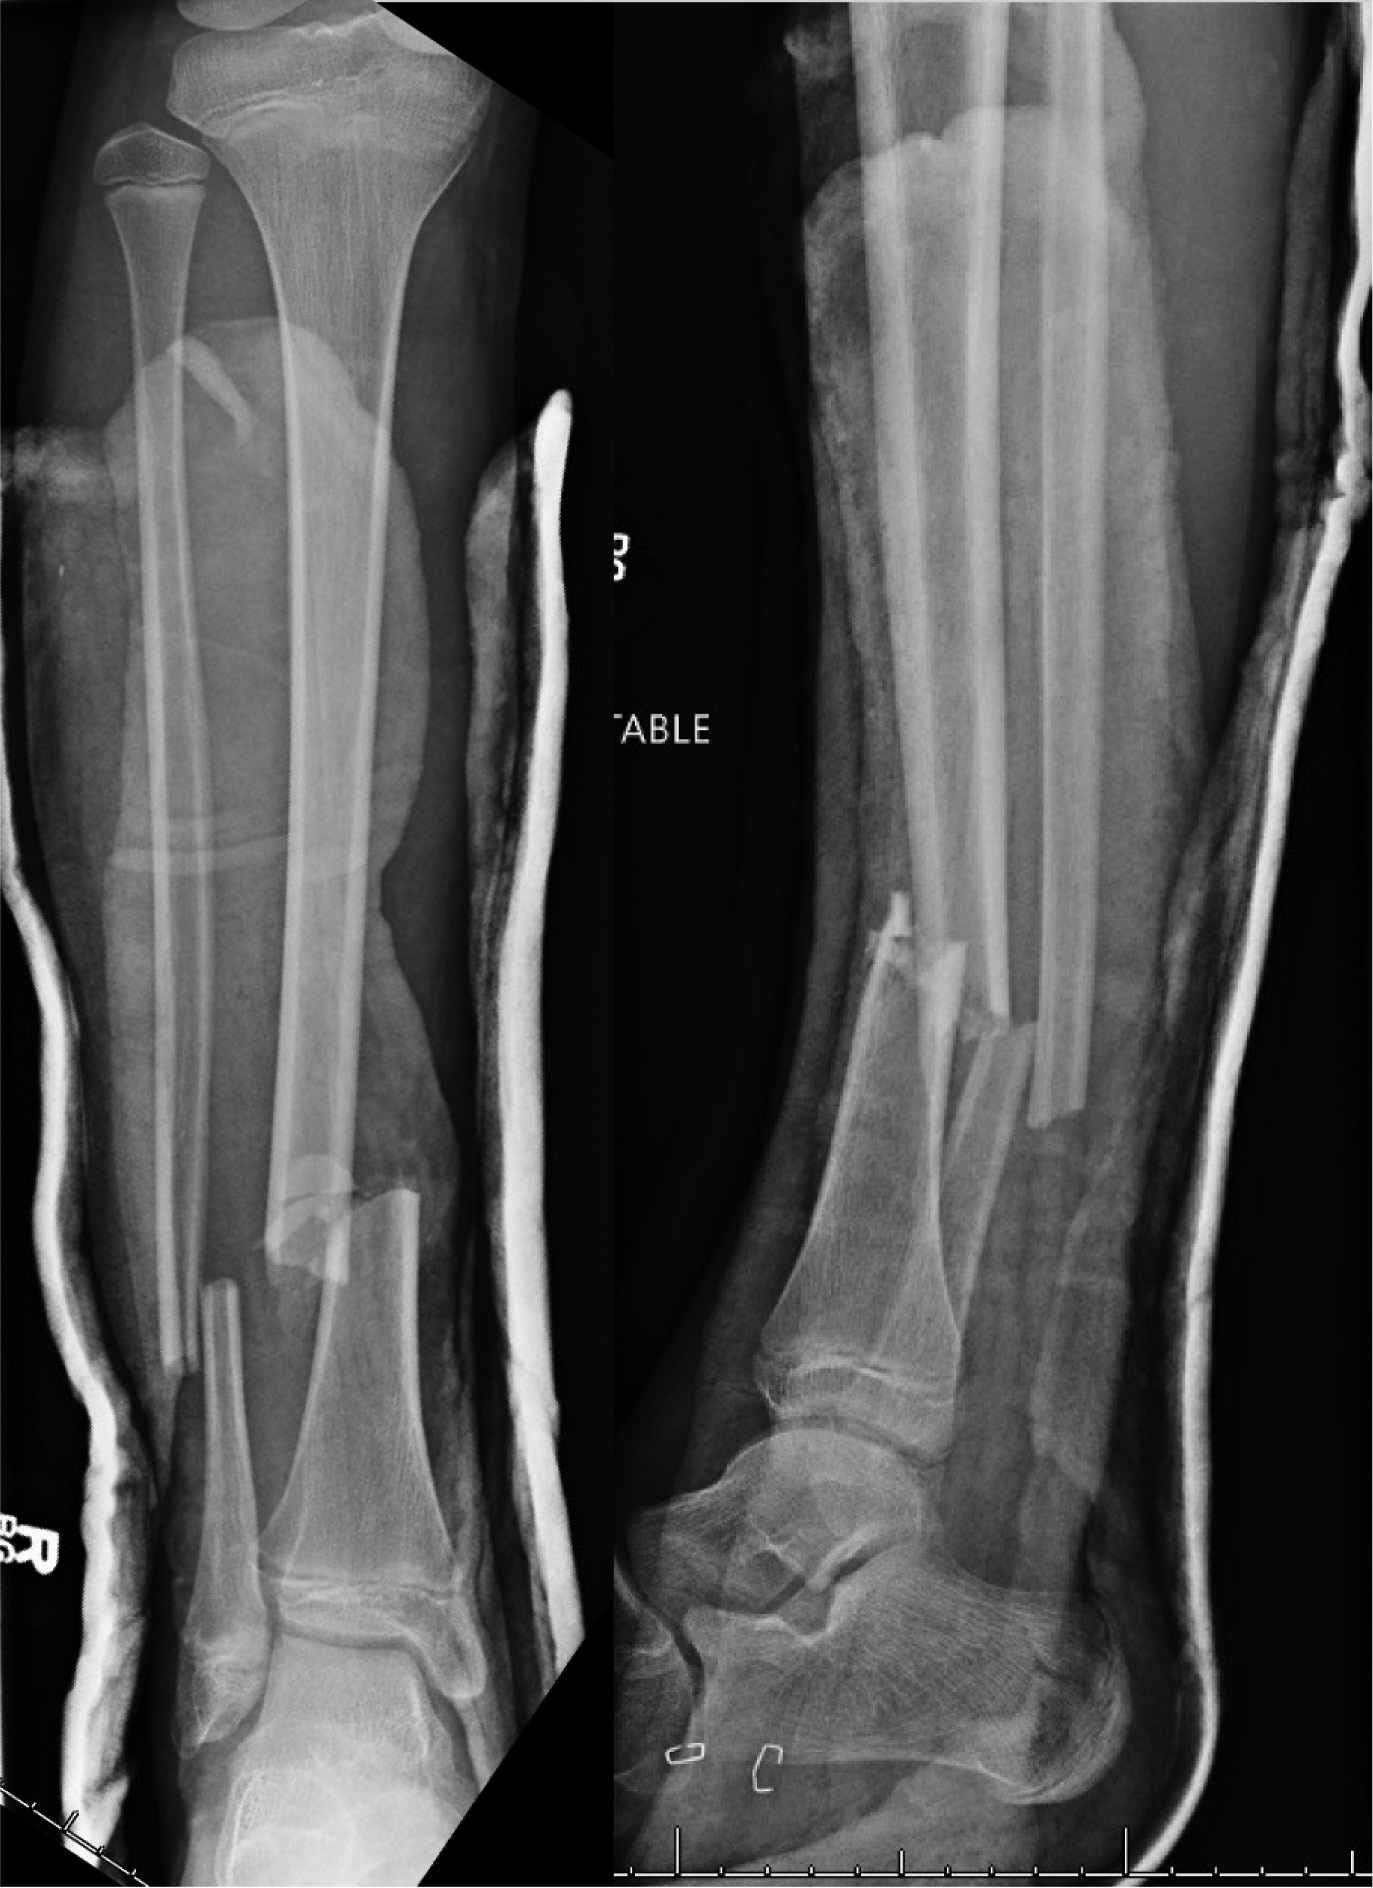

- Procedure and indication: R tibia and fibular ESIN for closed R diaphyseal tibia fracture with associated fibula fracture

- Alternatives considered:

- Difficulty with closed reduction, due to some of the comminution. Able to achieve good reduction by applying axial traction using radiolucent triangles and stack of blue OR towels.

- Tibia: 3.5 mm stainless steel ESINs

- Notice distally how the nails cross essentially right at the fracture. This is not ideal, but sometimes there is no way around this.

- Fibula: 1.5 mm titanium ESIN

- Decided to augment our tibial fixation with fixation of the fibula due to there being lateral comminution at the fracture on the tibia. We thought that by adding some stiffness/fixation to the fibula, we could help prevent the tibia from translating laterally and/or falling into valgus.